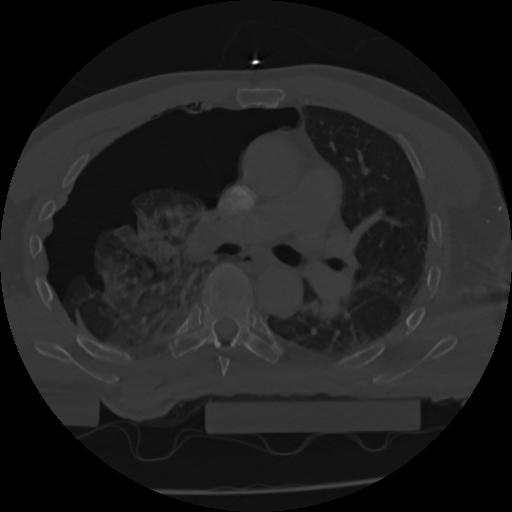

22 ANGIO,CE,Vol,0.5,ANGIO,,